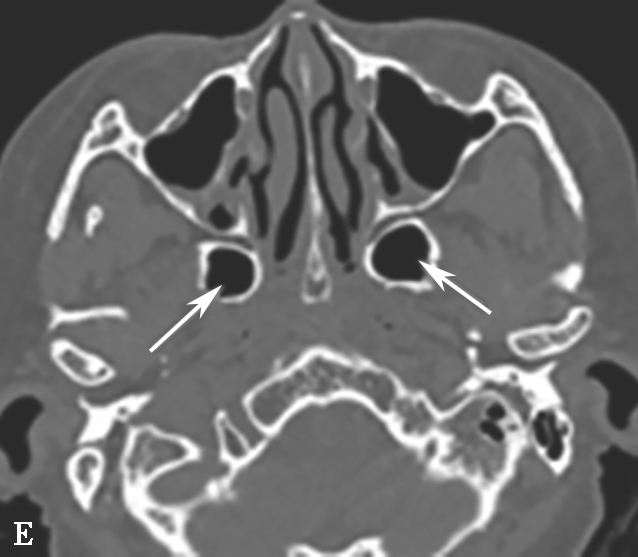

图1-3-7 蝶窦及蝶窦区解剖变异

A.颈内动脉管突入蝶窦;B.蝶窦间隔(白箭);C.左侧翼突气化;D.蝶嵴(星)、蝶骨大翼(白箭)、鞍背气化(虚箭);E.蝶骨小翼气化(白箭);F、G.鞍前型蝶窦(三角);H、I.甲介型蝶窦;J、K.鞍型蝶窦;L.Odoni气房(白箭)